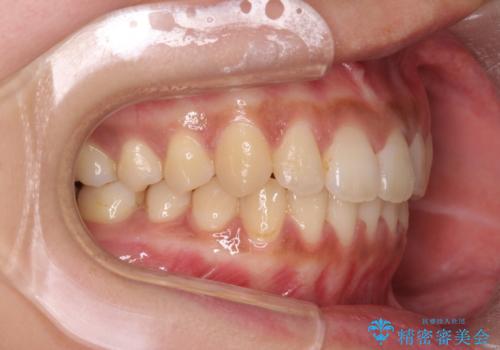

前歯のがたつきをすっきり マウスピース矯正

- 長年気になっていた前歯のがたつきをマウスピース矯正で治したい!と希望され来院されました。

奥歯の噛み合わせには問題がなく、前歯のがたつきの改善のみで十分に審美的な結果が得られるため、ワイヤーではなくマウスピース矯正での治療を計画します。

しっかりと前歯のがたつきは改善し見た目が大きく良くすることができました。